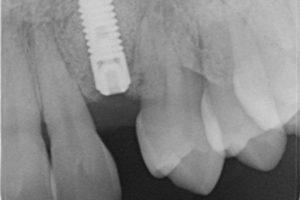

Regeneración de hueso en el suelo del seno maxilar para posibilitar la colocación de implantes y conseguir la restauración del espacio edéntulo con coronas fijas implantosoportadas.